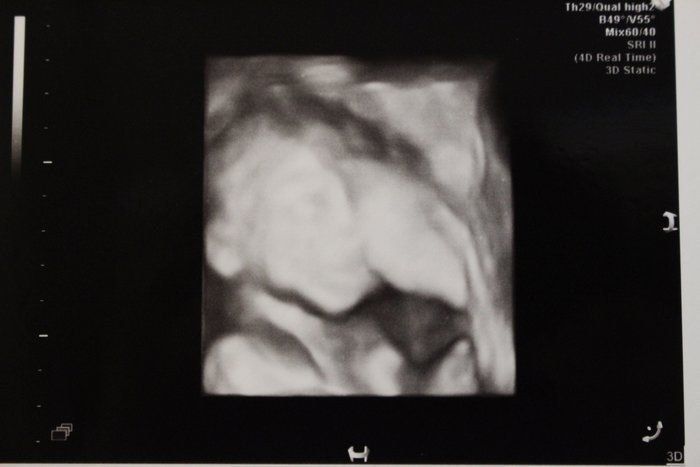

妊娠20週目の3D画像。早くも引っ込み思案な性格の表れか、エコー写真を撮ろうとすると胎盤の裏に隠れようとしています。何度も撮り直してようやく撮れたのがこちら。この頃、保健センターで催される母親学級で、産院が同じプレママと出会いました。